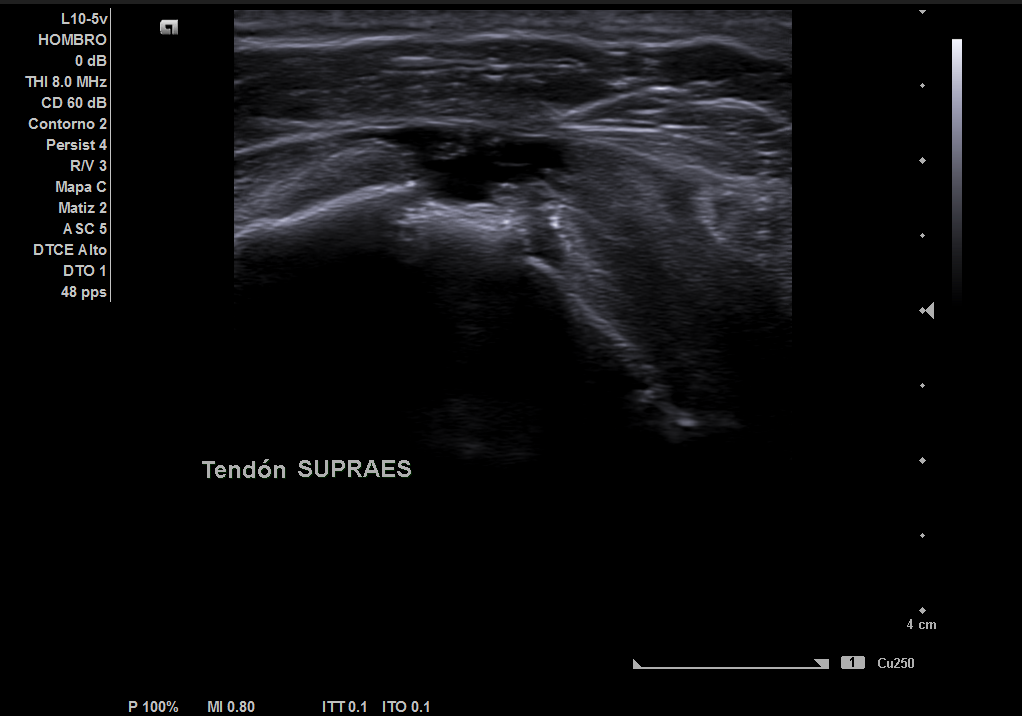

En la ecografía realizada observamos una rotura completa del tendón supraespino, rotura parcial del subescapular y severo derrame peritendón del bíceps junto con derrame articular glenohumeral.

Juicio diagnóstico: rotura manguito de los rotadores (rotura completa supraespinoso).